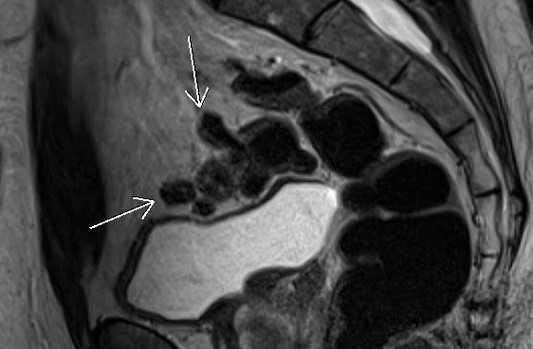

МРТ малого таза в сагиттальной плоскости. Отмечаются множественные дивертикулы сигмовидной кишки без признаков воспалительных изменений (стрелки).

МРТ малого таза в сагиттальной плоскости. Отмечается циркулярное утолщение стенок прямой кишки за счет наличия объемного образования (стрелка), распространяющегося за пределы органа в параректальную клетчатку.

МРТ малого таза в сагиттальной плоскости. МР-признаки анального транссфинктерного свища (линейной формы, стрелка). Наружное отверстие расположено на коже перианальной области на расстоянии 32 мм от анодермальной линии.